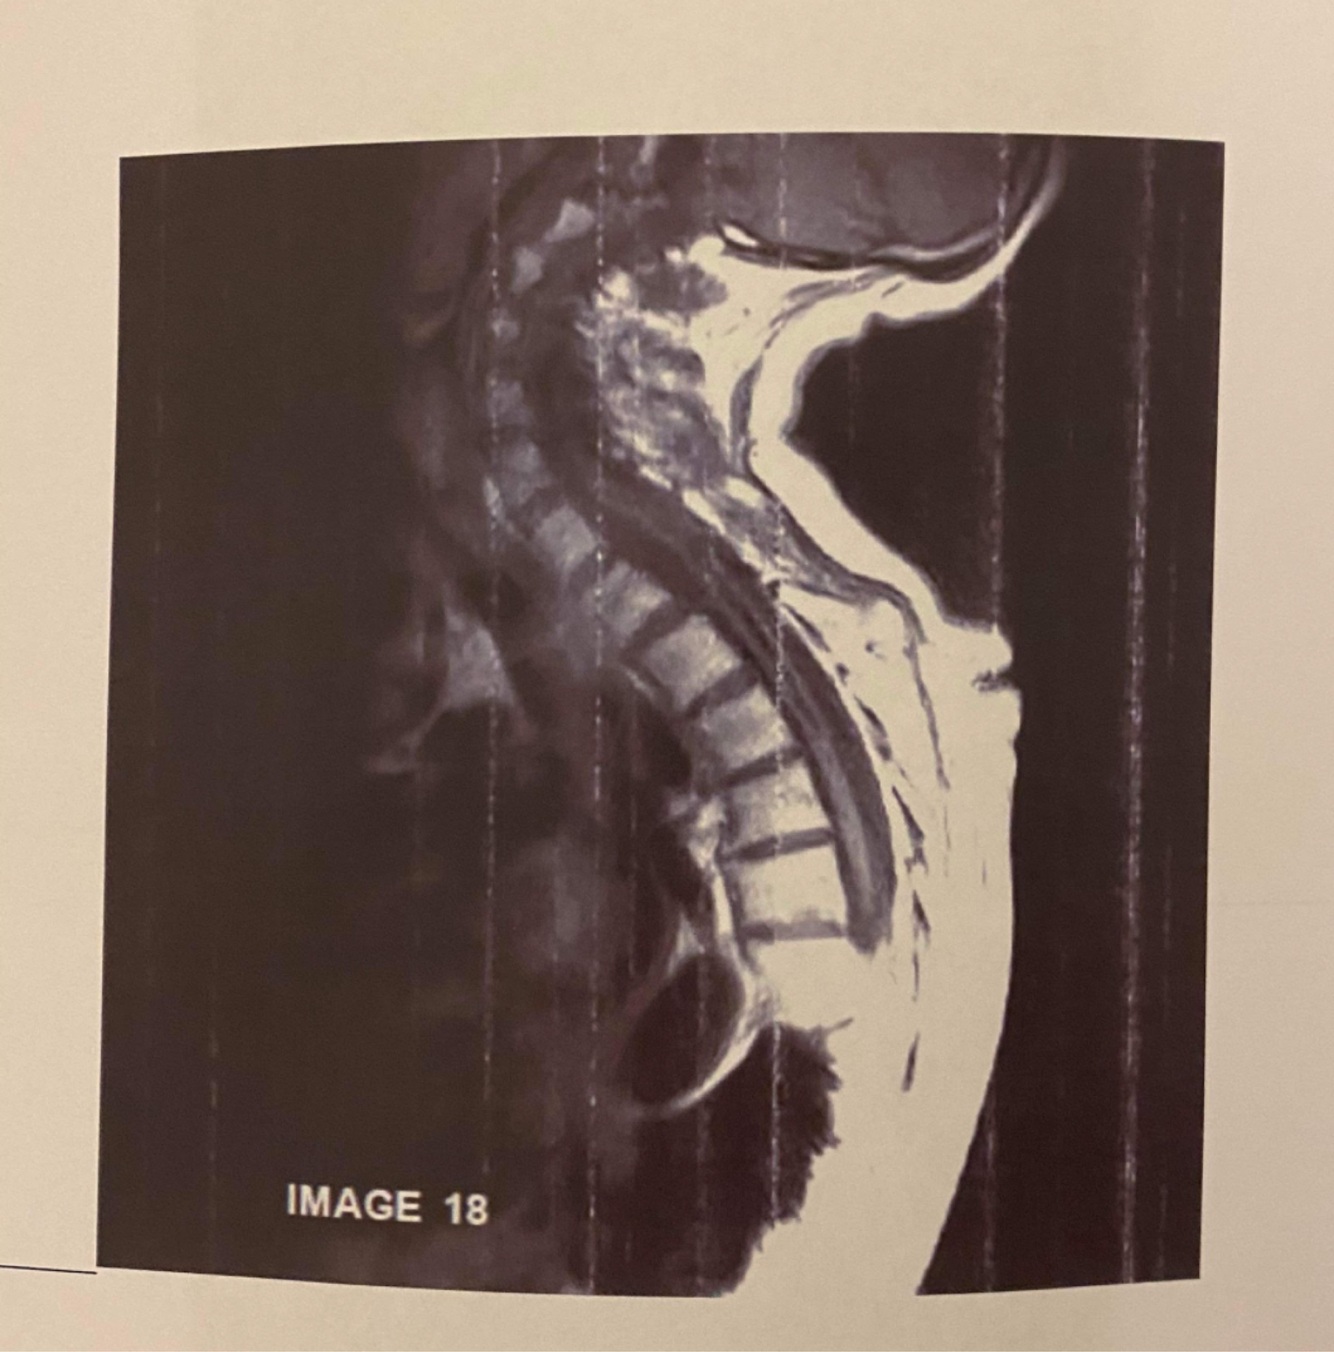

The Sag T2, demonstrates a post stenotic jet in which region?

Aqueduct of Sylvius